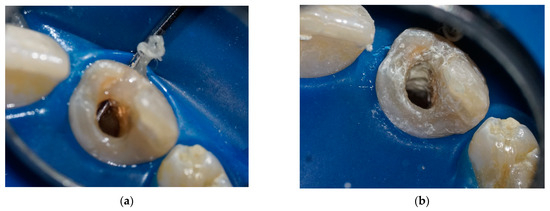

2. Detailed Case Description